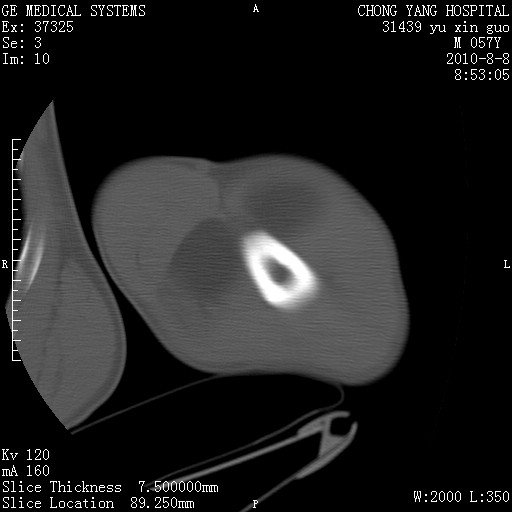

标题: CT28267:M57Y 上臂包块8年余。 [打印本页]

标题: CT28267:M57Y 上臂包块8年余。

典型脂肪瘤改变

包膜光滑、完整的脂肪密度肿块,支持脂肪瘤。